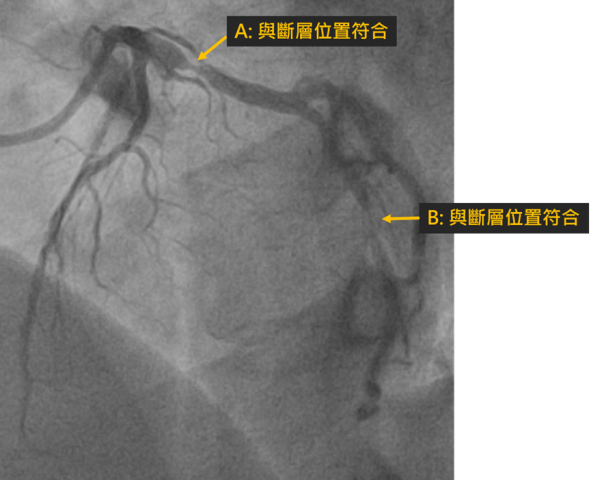

本院健檢中心成功偵測無症狀的嚴重冠狀動脈狹窄問題黃成偉醫師另外分享43歲林先生的案例,林先生任職於南科某高科技公司,至安南醫院健檢時,發現其冠狀動脈血管鈣化。雖然他自述平常無明顯症狀,且無高風險病史,但黃成偉醫師仍建議安排1024切電腦斷層,這才發現心臟冠狀動脈有多處嚴重狹窄;所幸,後續透過心導管支架置放,成功打通嚴重狹窄的血管,免於未來心臟病發作的風險。